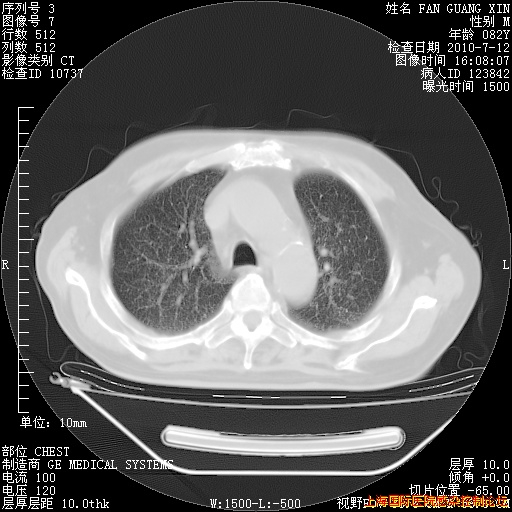

补发6月12日肺部CT肺窗

6月12日肺窗

6月12日纵膈窗